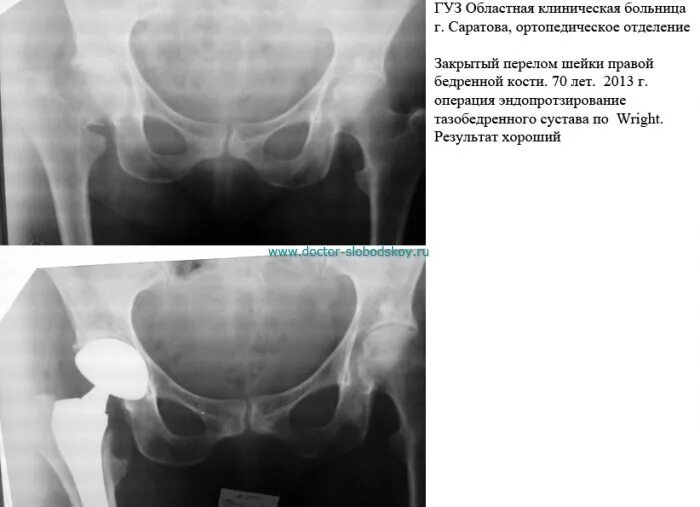

Перелом шейки бедра мкб 10 у взрослых